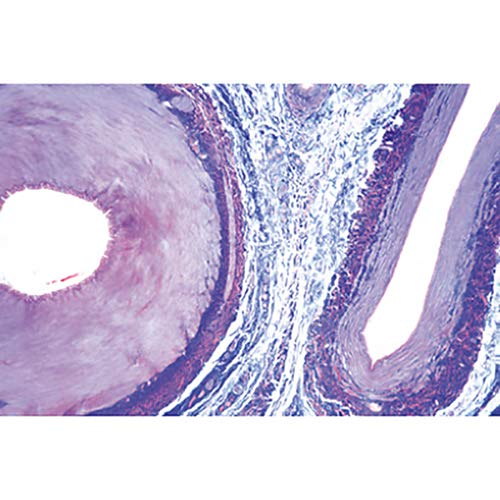

Microscope Slides: 1(d). Trachea, cat, t.s. 2(e). Lung, human t.s. 3(c). Blood, human, Wright stained smear 4(c). Artery, human, t.s., elastica stained